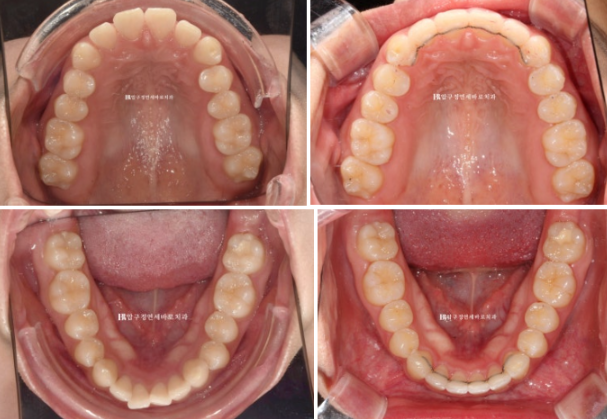

앞니 돌출로 교정을 위해 찾아온 환자분입니다.

24.02

앞니 좌우 높낮이가 다른 것이 보입니다.

어금니 교합은 좋습니다.

이렇게 어금니 교합이 좌우 I급이면 인비절라인 라이트의 완벽한 적응증입니다.

앞니 사이 벌어진 공간을 모으고 약간의 치간삭제를 동반하여 돌출감도 어느정도 해결하는 것을 목표로 삼았습니다.

인비절라인 라이트 권유드렸고 2월에 장치 오더 그리고 3월부터 1단계 장치를 끼기 시작했습니다.

24.10

24.02~24.10

뻗쳐있던 앞니 각도는 좋아졌고

공간도 깔끔하게 모아졌으며 배열도 좋습니다.

앞니를 뒤로 넣을 때 단순 뒤로만 움직이는 것이 아니라 위로 올리면서 함입하며 넣었기에 잇몸 노출량도 소량 줄었습니다.

일자로 떨어지는 앞니 각도는 세련된 인상을 줍니다

8개월 간 변화 소개입니다.